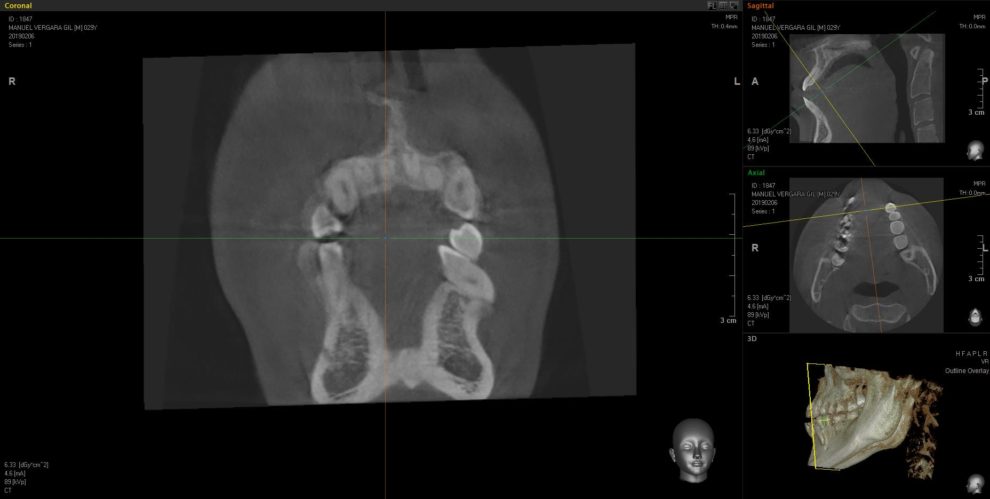

Ortodoncia + Mordida abierta

Nuestro paciente Manuel Vergara Gil acudió a nuestra clínica, y se le hizo una Ortodoncia.